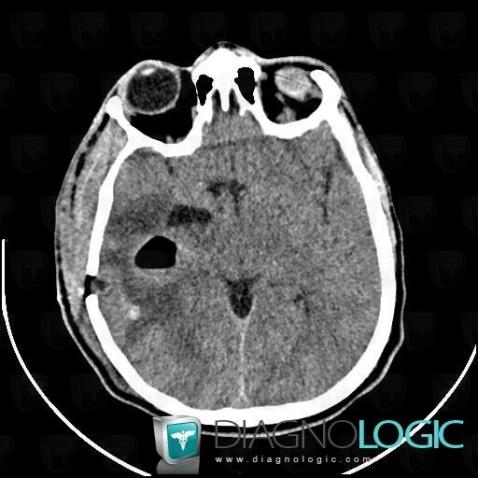

Abscess, Cerebral hemispheres, CT

Here is the specific information in the key image above:

- Diagnosis Abscess, Location(s) Cerebral hemispheres, with gamuts Hypodense intracerebral lesion on noncontrast CT